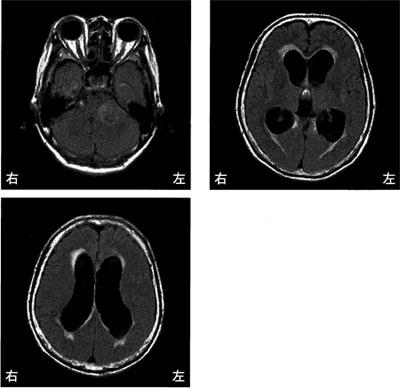

脳梗塞の発生部位によって出現する症状は異なります。この問題では、それぞれの部位における症状を正確に理解することが求められています。

Broca領域は運動性失語の症状が現れる部位であり、遂行機能障害は前頭葉で見られるため、この選択肢は誤りです。

右小脳半球では、右(同側)上下肢の運動失調が見られるため、この選択肢は誤りです。小脳半球の症状には、同側上下肢の運動失調や筋緊張の低下が含まれます。

右内包後脚では、左上下肢の運動麻痺が見られるため、この選択肢は正しいです。

左前頭葉では非流暢性失語が見られるため、この選択肢は誤りです。左半側空間無視は、右頭頂葉後部で見られる症状です。

左放線冠は部位によって様々な症状が現れますが、感覚性失語はWernicke領域で見られるため、この選択肢は誤りです。